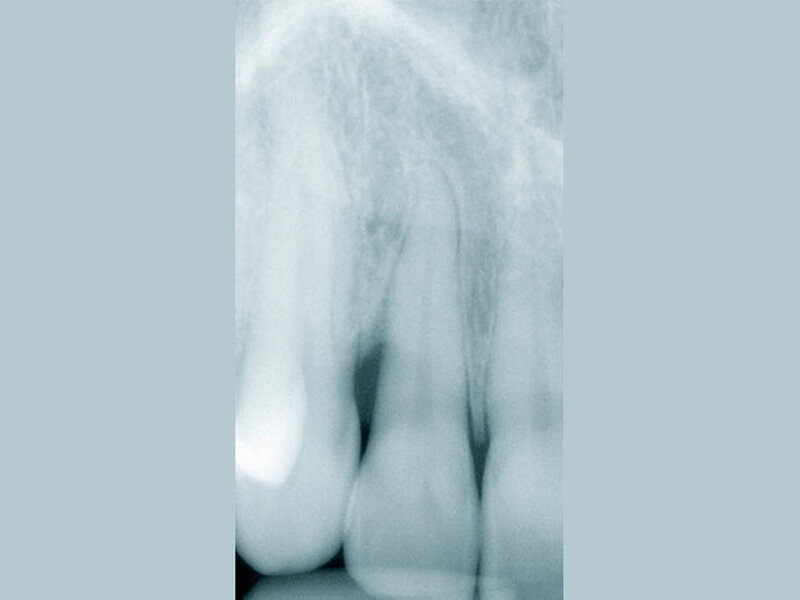

Ergebnis: Mithilfe der zusätzlichen Anwendung des mit Chlorhexidin beschickten Medikamententrägers konnte im Rahmen der gewählten unterstützenden Parodontitistherapie die parodontale Tasche lokal erfolgreich behandelt werden. Dies ist auch im Röntgenbild erkennbar (Abb. 4), das den radiologisch konsolidierten Knochenanbau am distalen Bereich deutlich zeigt.